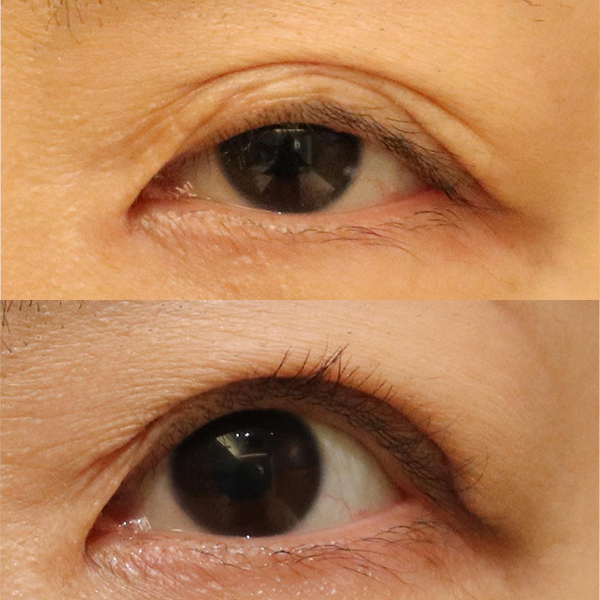

手術後眼瞼の形がおかしくなったため、再度C病院形成外科で修正の手術(皮膚切除)をしたが、やはり眼瞼の形が変だとのことで修正希望にて来院。

察すると前医の手術で重瞼がきっちり作成されているのですが、高すぎる位置に重瞼が作成されています。よく美容外科や形成外科で眼瞼下垂の手術を受けた術後で同様の状態になっている方を見かけます。

重瞼の位置は高ければよい、というものでは無いのです。重瞼は適切な位置でないと、その下の皮膚がたるんでしまってこのような状態になります。

黒目の大きさは大きくなったのですが、相対的に皮膚弛緩が強くなってしまっており、さらに重瞼の位置が不自然。当院での手術は不適切な位置の重瞼を含めて追加で皮膚切除、適切な位置に重瞼を作成しました。

術前は見開いたような目つきでしたが、術後には改善しているのが分かると思います。

| 術前 | 二重瞼にはなっているものの位置が上過ぎて結局その下の皮膚がたるんでいるため、しっかり開瞼出来ない状態 |

|---|---|

| 術後 | 重瞼の位置を睫毛上5ミリまで下げ追加で皮膚切除、二重瞼を作成した術前の不自然な皮膚弛緩は改善 |

| 術前 | 二重瞼の下の皮膚がたるんでいるためしっかり開瞼出来ない。そのせいで、見開いたような目つきになっている |

|---|---|

| 術後 | 当初より下方に二重瞼を作成し追加皮膚切除。術前の不自然な皮膚弛緩は消失し見開いたような目つきも改善 |

| 主訴 | 二重瞼の下の皮膚がたるみ、しっかり開瞼できないため見開いたような目つきになっている |

|---|---|

| 治療費 |

軽度なもの(15分程度):¥638,000 重度なもの:¥1,210,000 |

| 治療内容 | 不適切な位置の重瞼を含めて追加で皮膚切除、適切な位置に重瞼を作成 |

| 治療のリスク | 手術により創部が腫れ、内出血が起こります。翌日にはとても腫れます。腫れの消退は最初の2週間で8割程度改善し、完全な消退には約6ヵ月かかります。内出血(アザ)の完全な消退には4週間程度かかります。 |